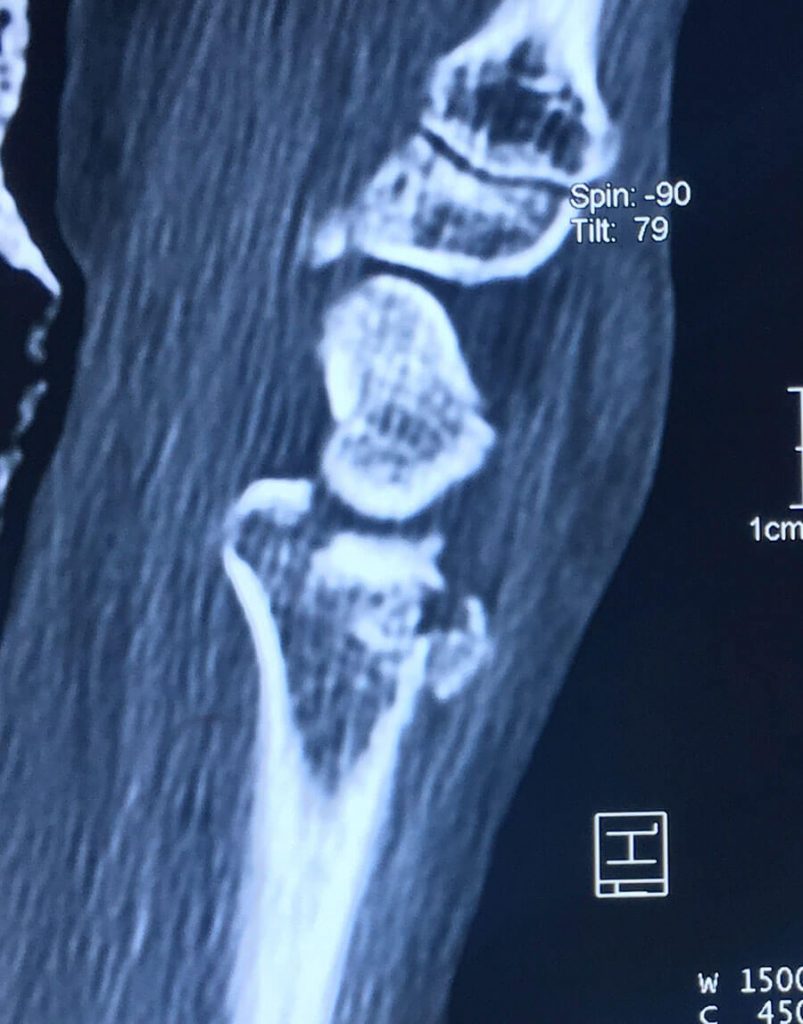

Esta radiografía del momento demostró una fractura tipo impactación de su radio dista en que la superficie articular se perdió completamente con un hundimiento central muy importante, si esto se dejara así el desarrollo de artrosis de esta articulación a corto plazo seria muy importante dejando una muñeca muy dolorosa casi para cualquier actividad, así que nos obliga a realizar una resolución quirúrgica.